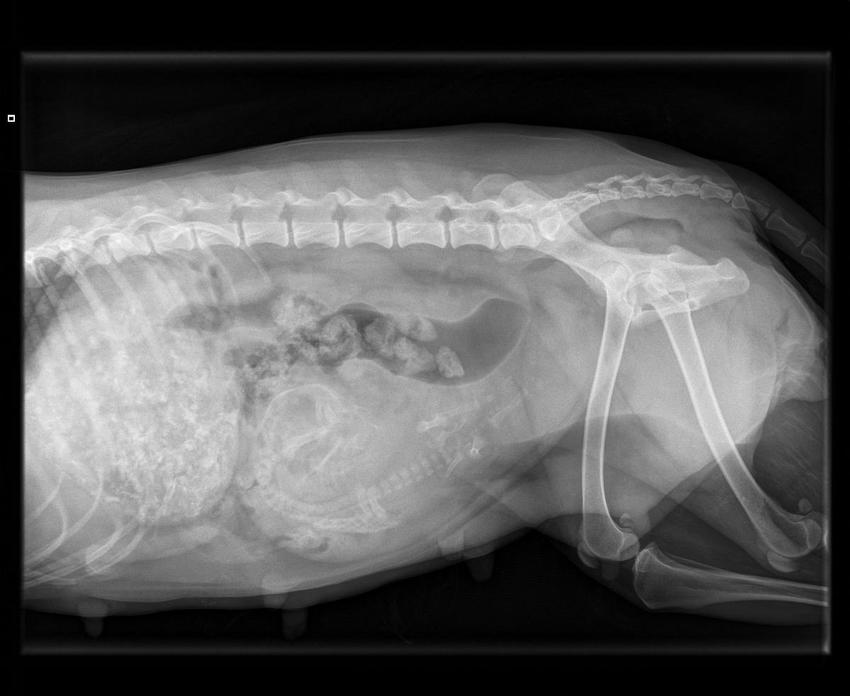

Na 4 merle pups, 2 reuen en 2 teven bleef Blue maar persen. Helaas zonder resultaat.... Daarom zijn we met haar naar de dierenarts gegaan. Deze heeft een foto gemaakt:

Op de foto is te zien dat er nog 1 pup helemaal vooraan bij de ribben ligt. De pup ligt gebogen en in een vreemde houding. We bereiden ons voor op een dode pup of een pup met een afwijking. Omdat de pup er toch uit moet krijgt Blue een keizersnede om de pup er uit te halen.